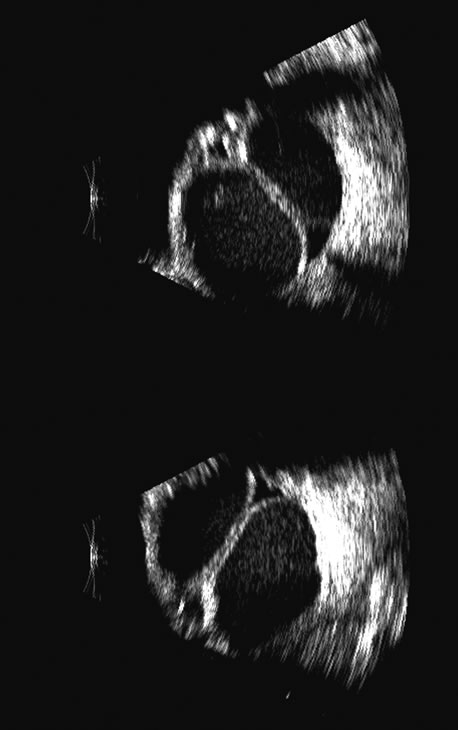

Spectral parameter imaging, a digital signal processing technique that examines the frequency content of backscattered ultrasound signals, has been shown to be predictive of increased lethality in certain patients and also to be useful in the in-vivo identification of high-risk melanomas for treatment staging.46–48 The shape, density, orientation, and number of scattering elements in a region influence not only the relative amplitude or brightness of a pixel on B-scan but the frequency content of the signal returned to the transducer.19 The concept of differentiating tissue backscatter in a quantitative manner rather than in simple qualitative descriptions of hypo-, iso-, and hyperechoic variations in gray scale allows for maximum use of information available in the digital ultrasonograms. These techniques can be extended to examining the functional anatomy of the eye as well as disease states other than solid tumors (Fig. 26).

Fig. 26. A gray-scale B-scan of a large collar-button melanoma (top) showing a relatively isoechoic button and base with some differences in internal speckle noted. The companion serial plane spectral parameter image (bottom) shows local differences in the size of ultrasound scatterers within the tumor, with size range increasing from blue to red.